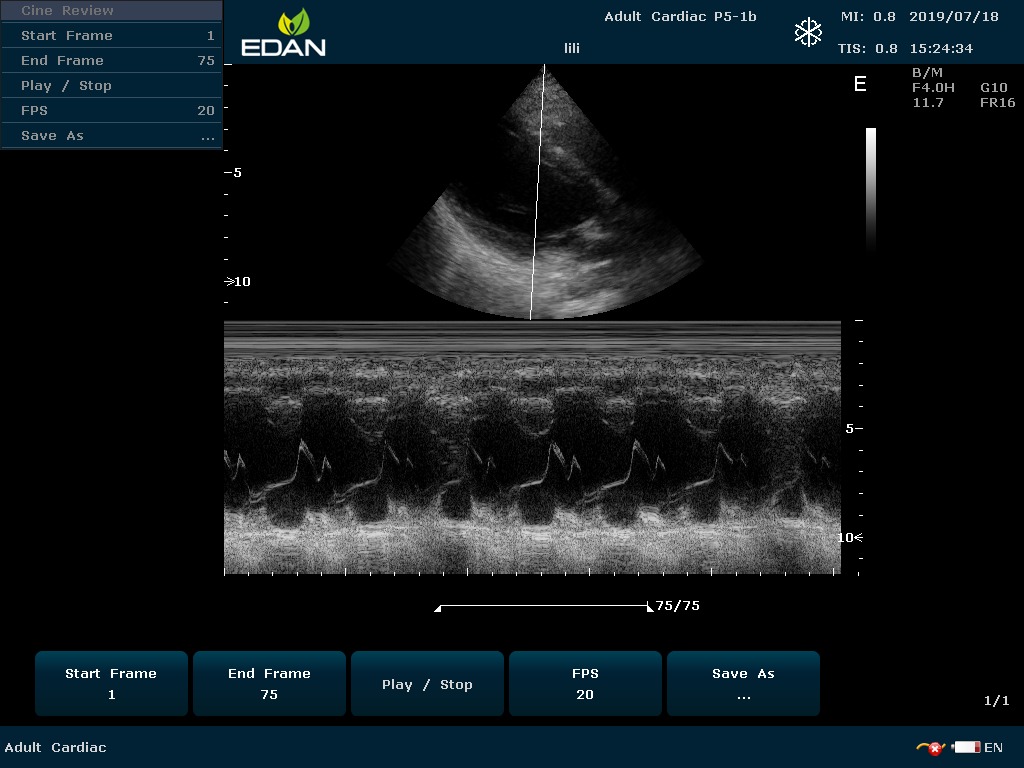

Особенность U60 Edan — расширенное применение. Ультразвуковой аппарат рекомендован для абдоминальных исследований, гинекологии и акушерства, кардиологии, педиатрии, урологии, изучения малых органов, сосудов. Для U60 Edan используются конвексные, линейные, фазированные и внутриполостные датчики.

Передовые технологии позволяют повысить качество визуализации в несколько раз. УЗИ-аппарат U60 Edan отличается возможностью быстрой настройки визуализации. Специальные функции позволяют моментально отображать данные за счет быстрой оптимизации параметров. Режимы визуализации: B-mode, M-mode, Color Doppler, Power Doppler Imaging, Pulsed Wave Doppler, Continuous Doppler.